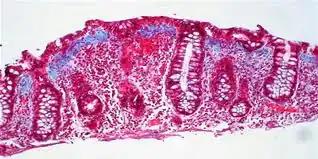

![]() Un aumento del número de linfocitos epiteliales con una inflamación anormal a nivel microscópico. | ||

El diagnóstico se hace gracias al estudio microscópico de las biopsias de colon, ya que el resto de las exploraciones habitualmente hechas a estos pacientes (análisis, estudios radiológicos, colonoscopia) suelen ser normales o mostrar hallazgos inespecíficos sin valor diagnóstico. El estudio de las biopsias permite distinguir entre los dos subtipos más frecuentes de colitis microscópicas: la colitis colágena, definida por la presencia de una banda gruesa de fibras colágenas por debajo del epitelio (células que recubren el intestino por dentro), y la colitis linfocítica, en la que hay acúmulo de linfocitos en número excesivo a nivel del epitelio del colon. Existen casos mixtos, en los que no se puede distinguir entre ambos procesos, que por lo demás comparten unas características clínicas comunes. A veces la afectación colónica es parcheada, por lo que, si la sospecha clínica es elevada, es conveniente tomar múltiples biopsias de colon en sus diferentes tramos, lo cual aumenta la rentabilidad diagnóstica. La afectación suele ser más grave a nivel de colon derecho.